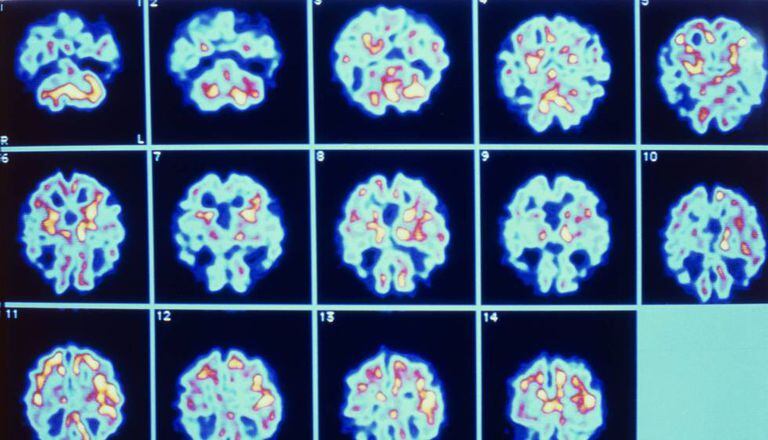

Infelizmente, a pesquisa do Alzheimer está particularmente recheada de obstáculos, incógnitas e frustrações. Para começar, não sabemos ainda o que provoca a doença. Sabemos que a genética e os fatores ambientais têm seu papel, mas isso não é de grande ajuda. Também não estamos certos de como se desencadeia a doença ainda que exista uma descoberta típica para confirmar o diagnóstico de Alzheimer: Presença de placas de beta amiloide e novelos neurofibrilares de tau no cérebro de uma pessoa com demência. Mas essas placas e novelos são causa ou consequência da doença? O certo é que, atualmente, não sabemos.

Durante muitos anos, existiram principalmente três posturas sobre como a doença progride. A corrente majoritária afirma que são as placas de peptídeos beta amiloide que provocam a morte dos neurônios. De fato, a ampla maioria dos mais de 100 testes clínicos em andamento para o Alzheimer são tratamentos dirigidos ao peptídeo beta amiloide. Outro grupo, menos numeroso, defende que são os novelos neurofibrilares da proteína tau os que realmente matam os neurônios. Por outro lado, também existe um grupo de pessoas que pensa que, ainda que os dois fatores desempenhem certo papel na evolução da doença, poderia ser outra coisa que está realmente danificando os neurônios e que ainda não identificamos.

São todas essas razões e muitas outras que poderiam explicar por que tratamentos eficientes em roedores não estão funcionando em humanos... mas há algo mais. Muito antes de que uma pessoa comece a notar as primeiras lacunas de memória, no cérebro já ocorreram mudanças biológicas que não foram detectadas ao não se realizarem os testes oportunos. É possível que os testes clínicos falhem porque os doentes estão sendo tratados em uma fase muito tardia, sem nenhuma oportunidade de reverter ou parar o processo? É a pergunta fundamental na pesquisa do Alzheimer. Justamente por isso, estão sendo destinados grandes esforços para se descobrir marcadores precoces da doença e começar os tratamentos experimentais bem cedo, antes do surgimento dos primeiros sintomas.